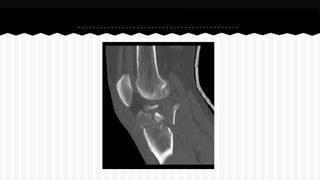

RESPONDA O NOME DO OSSO EM QUE

SE ENCONTRA A (S) FRATURA (A).